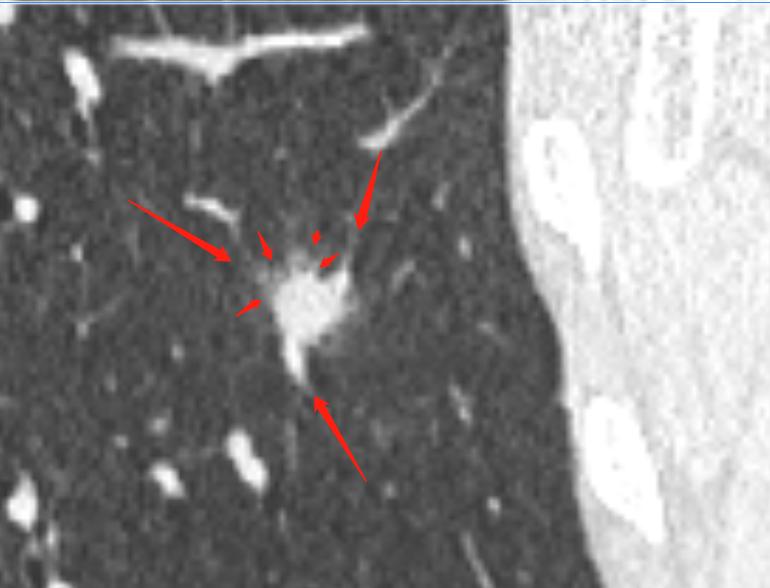

通过以上图片,病灶确实为实性结节,大小约1.0cm×0.9cm×1.0cm,呈浅分叶,周边可见毛刺,可见小血管穿入,但是影像学还是有一些不符合恶性肿瘤的特点:

1.病灶周边有一些渗出性改变。

2.相对1cm大小的肺结节来说,周边的毛刺有点长。

3.病灶及周边有扩张的支气管影。

4.病灶周边血管明显有贴边征象。